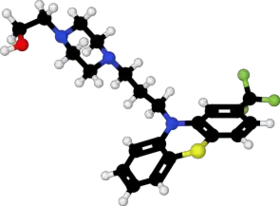

IUPAC name

| Formula | C22H26F3N3OS |

| Molar mass | 437.53 g·mol−1 |

SMILES

InChI

Fluphenazine is a typical antipsychotic of the phenothiazine class.[1] Its mechanism of action is not entirely clear but believed to be related to its ability to block dopamine receptors.[1] In up to 40% of those on long term phenothiazines, liver function tests become mildly abnormal.[5]